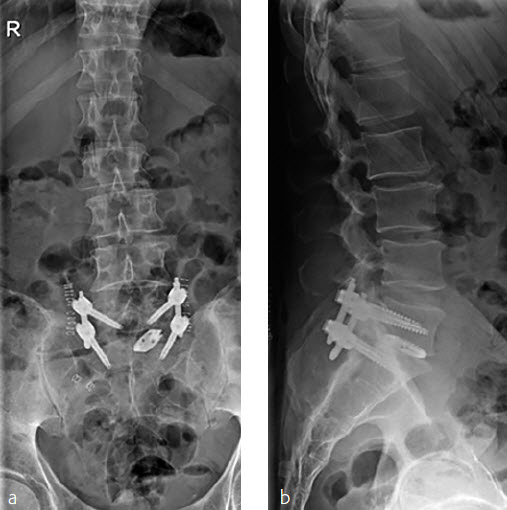

A 70-year-old woman with an adult spinal deformity (ASD) was referred to our hospital for a second opinion. Her medical history included rheumatoid arthritis for which she was given long-term methotrexate therapy and cures of corticosteroids. She presented with a severe degenerative deformity and right L3 radiculopathy. The patient was completely off balance with a right coronal shift and a positive sagittal balance with a SVA of 10 cm+ (Fig 4). Figure 5 reveals full spine images and pelvic parameters. She led a sedentary lifestyle because of the disturbance of balance and back and right leg pain. The patient opted for surgery after a shared decision process and informed consent.

The surgery was planned as a posterior approach to correct the spinal deformity and restore coronal as well as sagittal balance with direct and indirect decompression of the right L3 nerve root. The preoperative bone assessment and DEXA scan indicated osteopenia and considering her medical history the decision was to use cortical fix screws that also allowed cement augmentation.

We performed a posterior fusion and correction of Th8-S2-SI-Ilium (Fig 6). In Th9, Th10, Th11, and Th12 we instrumented only unilateral pedicle screws due to small pedicle diameters. A S2-SI-Ilium screw was placed on the left side. A supplemental translaminar screw was used at L5-S1 on the right side. We augmented the screws in Th8, Th9, Th10, L2, L3, and L4. Additionally, a TLIF approach was performed on L2-3 and L3-4 with autogenous bone as interbody support. No complications occurred during nor after surgery, and she remained in good balance during the 1-year postoperative follow-up.